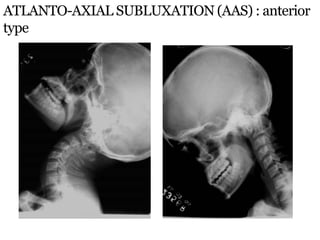

ATLANTO-AXIAL SUBLUXATION (AAS) : anterior

type

Anterior Atlanto-Dental Interval (AADI) :

 AAS is present when it is >3mm in adults & >5mm in

children

 Measured from posteroinferior margin of ant arch of C1

to the ant surface of odontoid

 AADI 3-6 mm  trans lig. damage

 AADI >6mm  alar lig. damage also

 AADI >9mm  surgical stabilization

ATLANTO-AXIAL SUBLUXATION (AAS) :

anterior type

Posterior Atlanto-Dental

Interval (PADI) :

** Distance b/w posterior

surface of odontoid &

anterior margin of post ring of

C1

 Considered better method as it

directly measures the spinal

canal

 Normal : 17-29 mm at C1

 PADI <14mm : predicts cord

compression

 X-rays in neutral position will miss AAS in 48%.

 Controlled flexion views always to be done